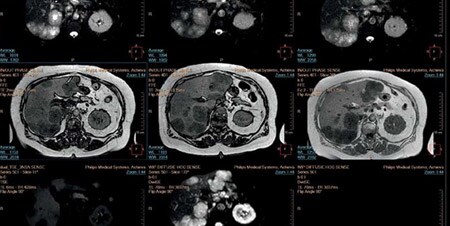

Our scalable radiology informatics platforms compile and deliver information from multiple sources to any workstation, even outside the hospital, so clinical decisions can be made at any time and from virtually anywhere. By integrating the data to show a full patient picture over time, we can enhance clinical decision support to help reduce the number of unnecessary scans.

Phoenix Children’s Hospital is using clinical informatics with adaptive intelligence to structure healthcare data across multiple sources and make the invisible, visible through medical data visualization*.

Features in the IntelliSpace PACS system help radiologists at Sint Franciscus Gasthuis in the Netherlands keep up with their increasing workload*.